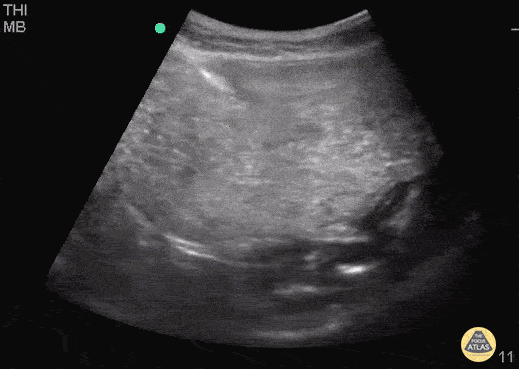

80 y/o demented M patient comes in with complaint of abdominal distention, noticed by caregivers. Patient "not keeping anything down." POCUS was done to visualize the "distention." Fluid is seen in what was presumably the stomach, moving forward and backward, not passing the pylorus. The distal bowel did not contain similar fluid. CT demonstrated gastric volvulus and GI was consulted. Dr. Bryan Jarrett - Kings County/SUNY Downstate Emergency Medicine